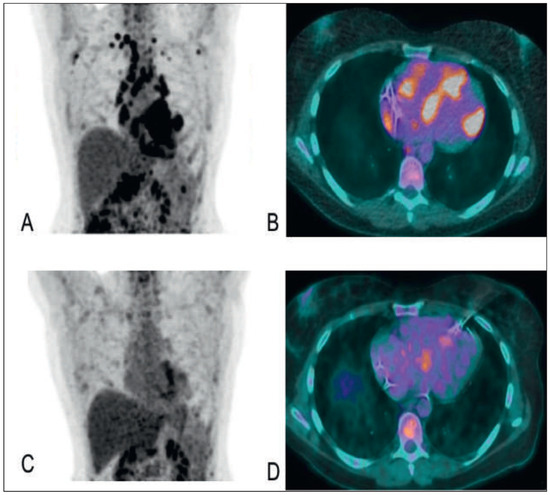

Cardiac Sarcoidosis with Coeliac Disease

by Stéphane Fournier, Julien Regamey, Samuel Rotman, Etienne Pruvot and Roger Hullin

Cardiovasc. Med. 2016, 19(4), 128; https://doi.org/10.4414/cvm.2016.00412 - 20 Apr 2016

This case of cardiac sarcoidosis started with manifestation of a complete atrioventricular block in a 42-year-old female without other cardiac dysfunction. Two years later, the patient presented with acute heart failure symptoms at the Emergency Department. Echocardiography at admission showed thinning and hyperdensity [...] Read more.

This case of cardiac sarcoidosis started with manifestation of a complete atrioventricular block in a 42-year-old female without other cardiac dysfunction. Two years later, the patient presented with acute heart failure symptoms at the Emergency Department. Echocardiography at admission showed thinning and hyperdensity of the basal interventricular septum, which is a rare but typical echocardiographic sign of cardiac sarcoidosis. Endomyocardial biopsy, positron emission tomography–computed t omography and transbronchial biopsy confirmed the clinical suspicion of sarcoidosis. Of note, the patient also had coeliac disease, which can occur conjointly with sarcoidosis. After 5 months of immunosuppressive treatment with methylprednisolone and azathioprine the burden of inflammatory lesions was significantly reduced and the patient had improved to New York Heart Association class I. Full article